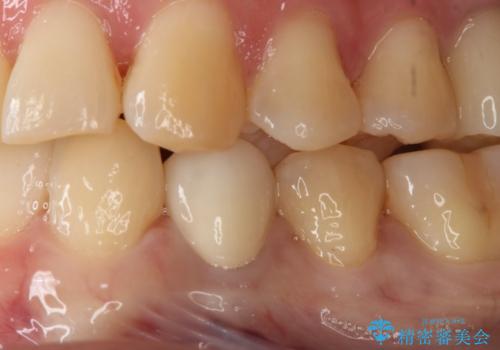

- 左下4番のう蝕を指摘され治療を希望された患者様です。

切削量などを考慮しクラウンでの治療を提案したところ、セラミックを希望されたのでフルジルコニアクラウンでの治療を選択しました。

う蝕が深かったので痛みが出る可能性をお伝えしましたが特に症状は現れなかったので、予定通りセラミッククラウンでの治療を行いました。